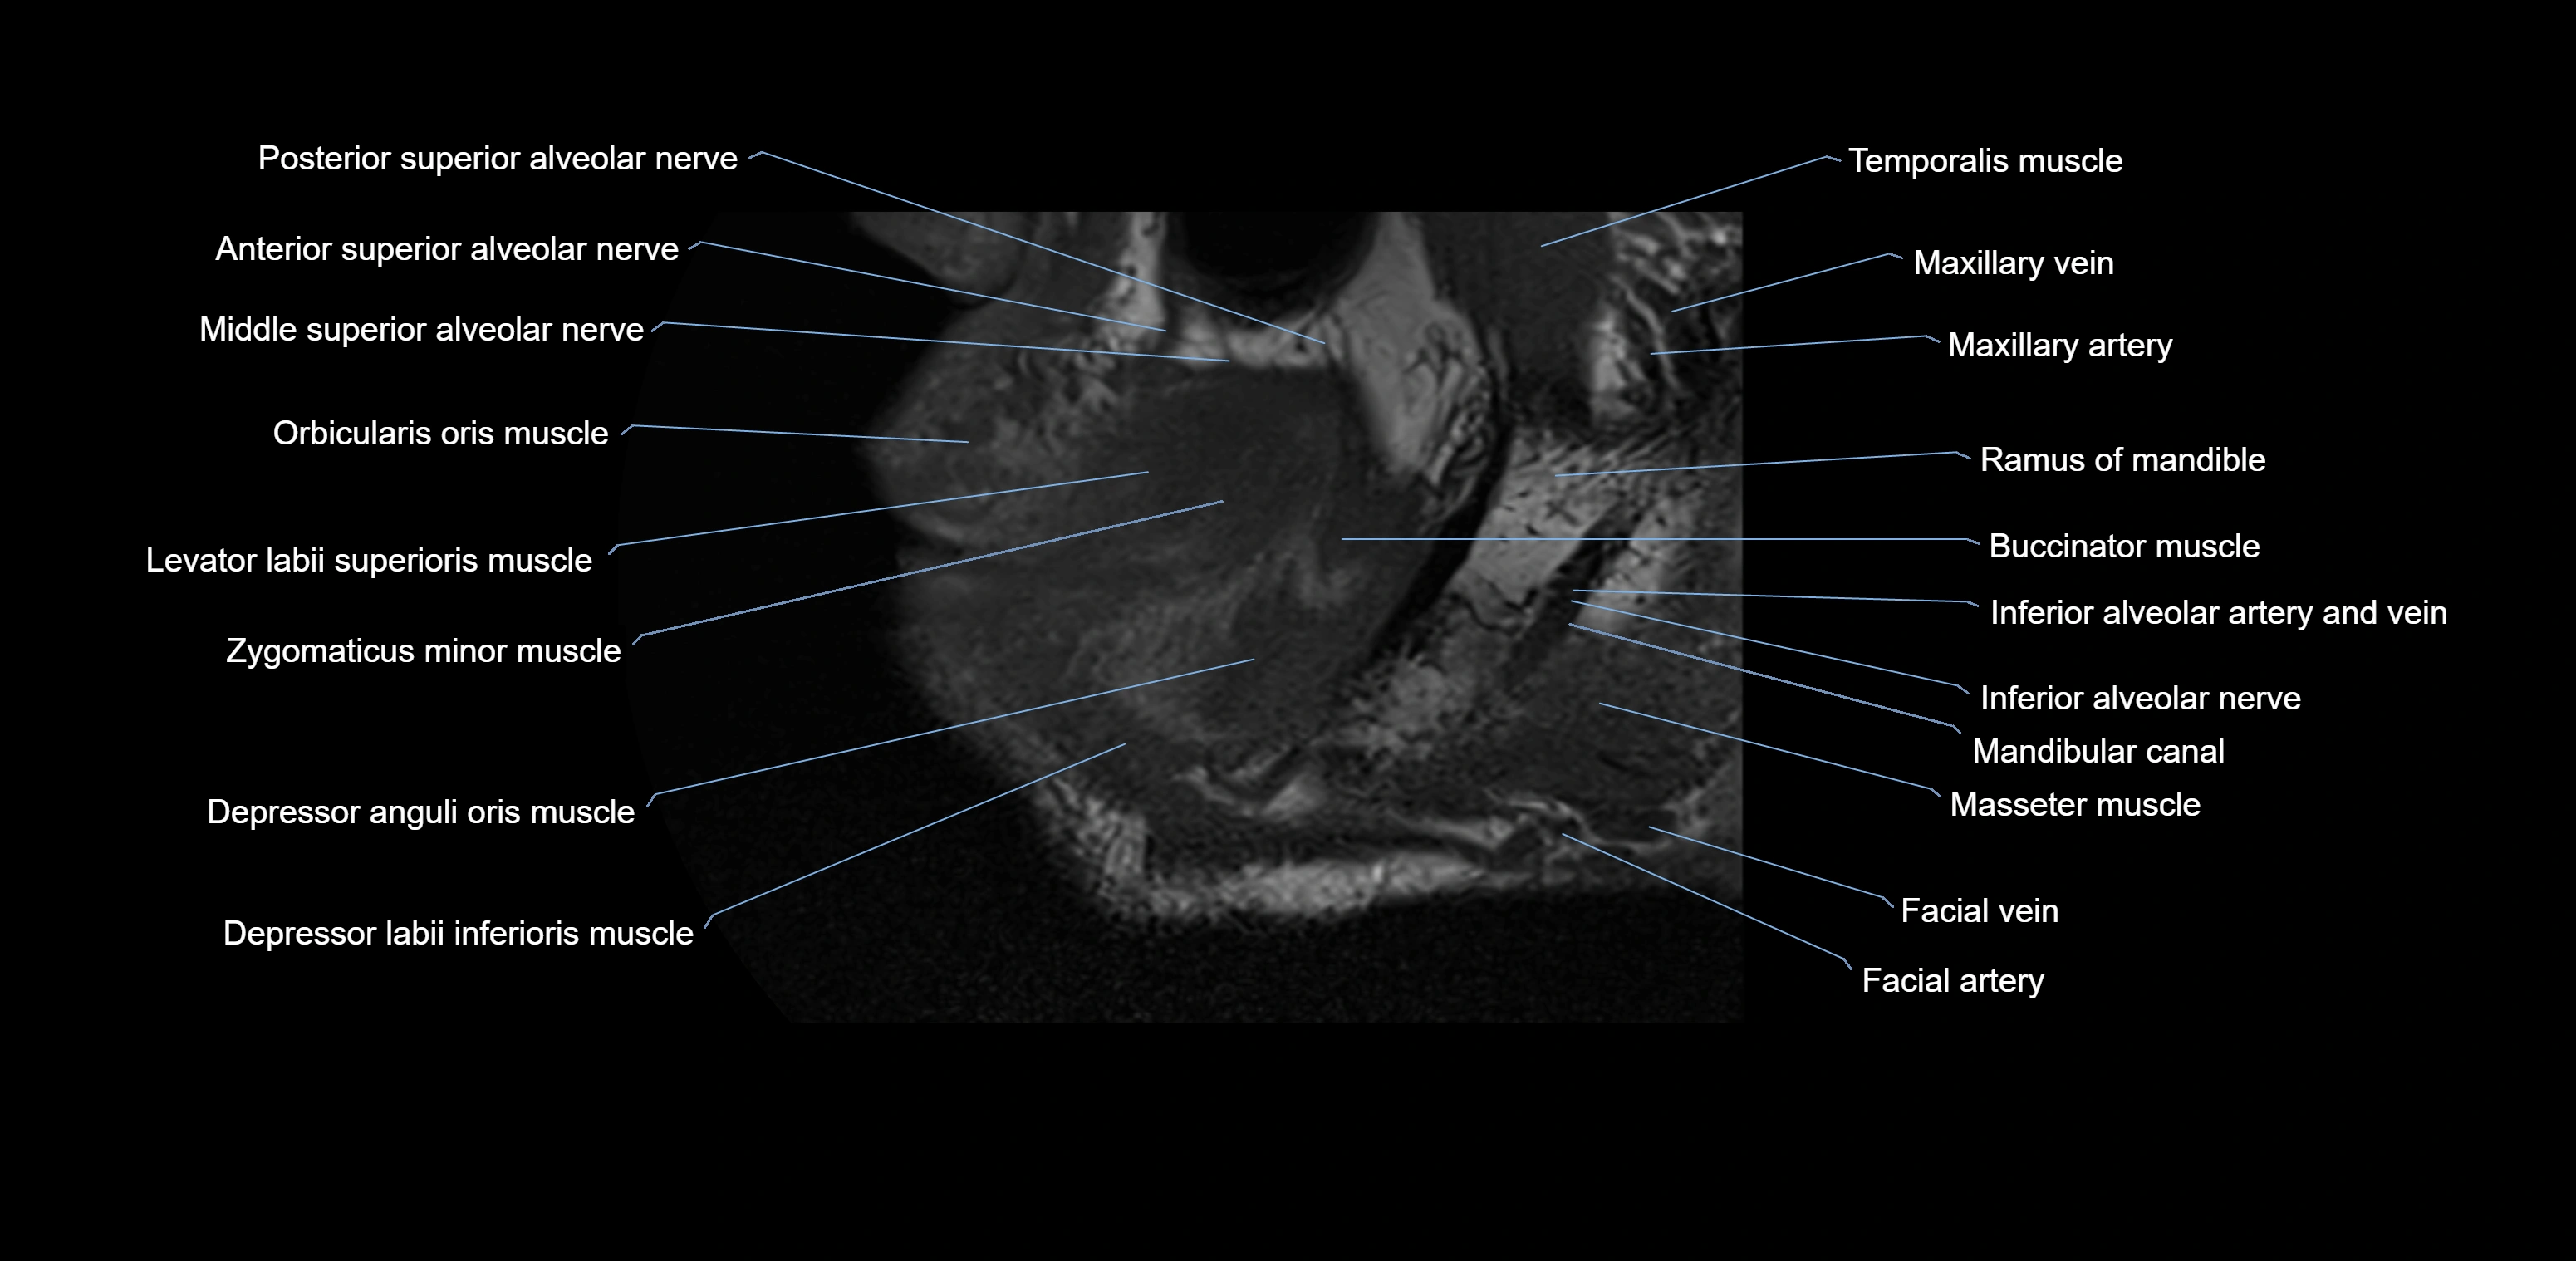

- Anterior superior alveolar nerve

- Buccinator muscle

- Inferior alveolar nerve

- Mandibular canal

- Middle superior alveolar nerve

- Orbicularis oris muscle

- Posterior superior alveolar nerve

- Ramus of mandible